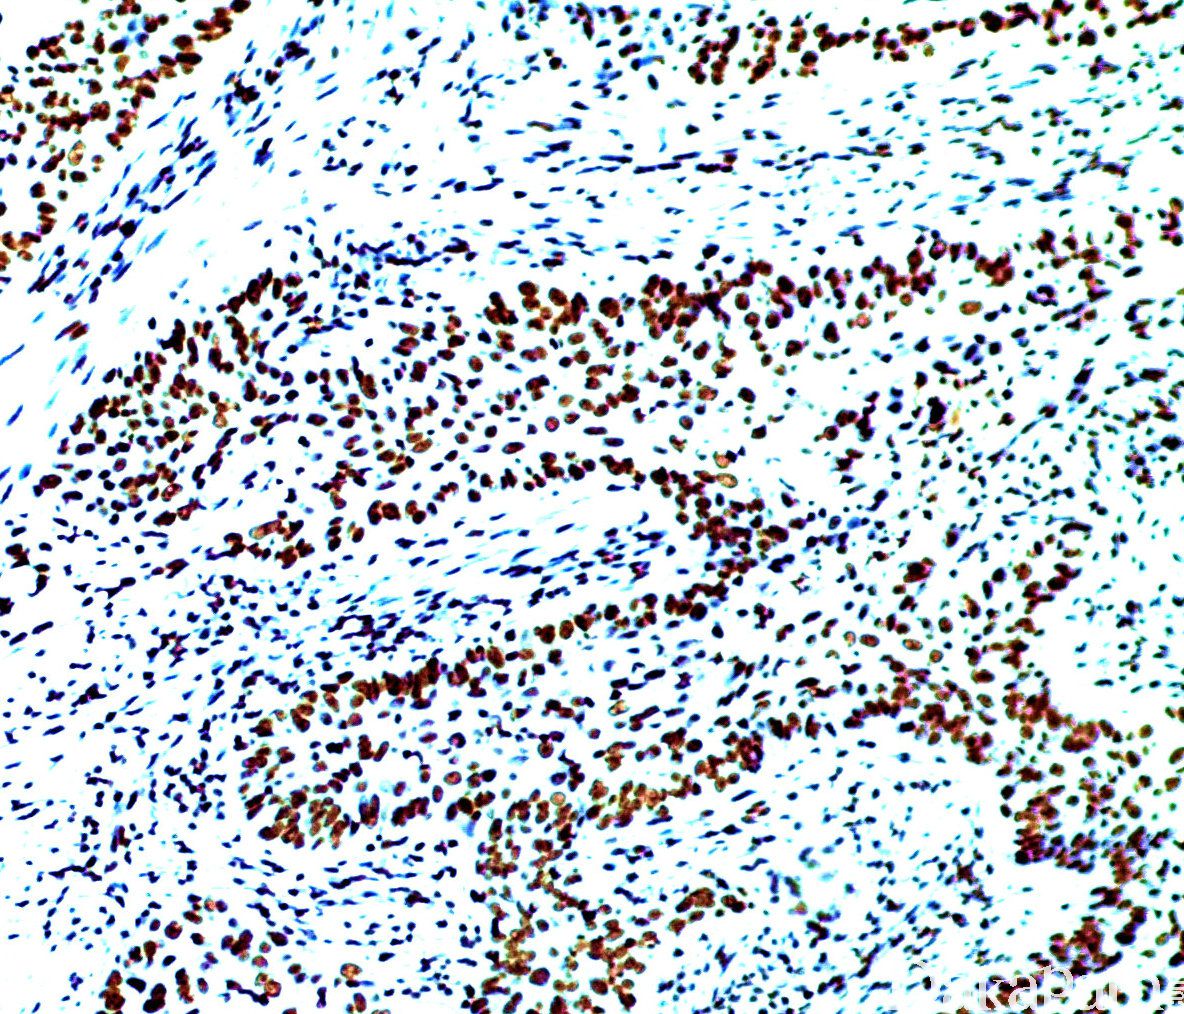

ERCC1

信号定位: 胞核

表达水平与肺非小细胞肺癌对以铂类为基础的化疗药物的敏感性有关(阳性患者可能耐药),对病理诊断无价值。